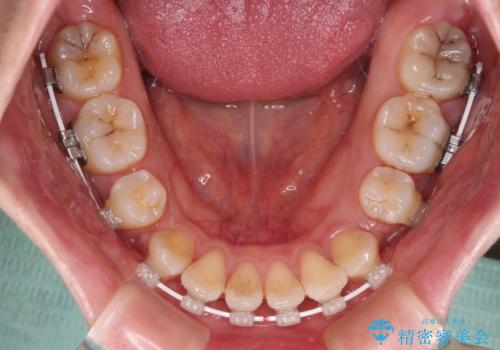

- 前歯のデコボコや口元の突出感、口の閉じにくさを気にして来院された患者様です。

上下左右第一小臼歯4本を抜歯し、ワイヤー装置にてデコボコを解消しながら口元を引っ込めるよう矯正治療を行うこととしました。

抜歯スペースを閉じている過程で、左側の上下犬歯が引っかかってしまい、進捗が停滞しましたが、当初予定の2年~2年半の間で無事に治療を終えることができました。